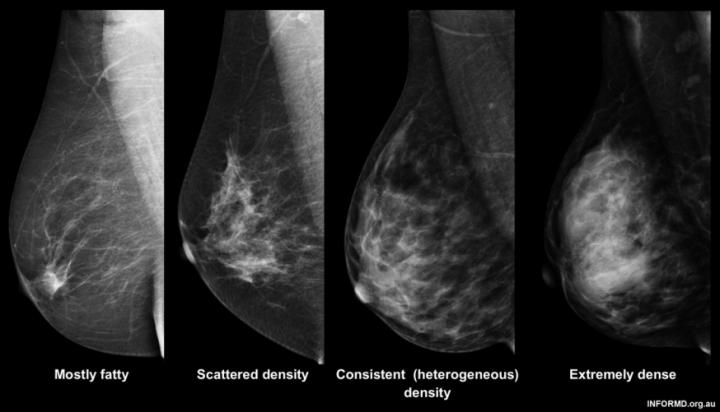

Almost 8% of women have extremely high breast density and are more likely to develop breast cancer in the future.